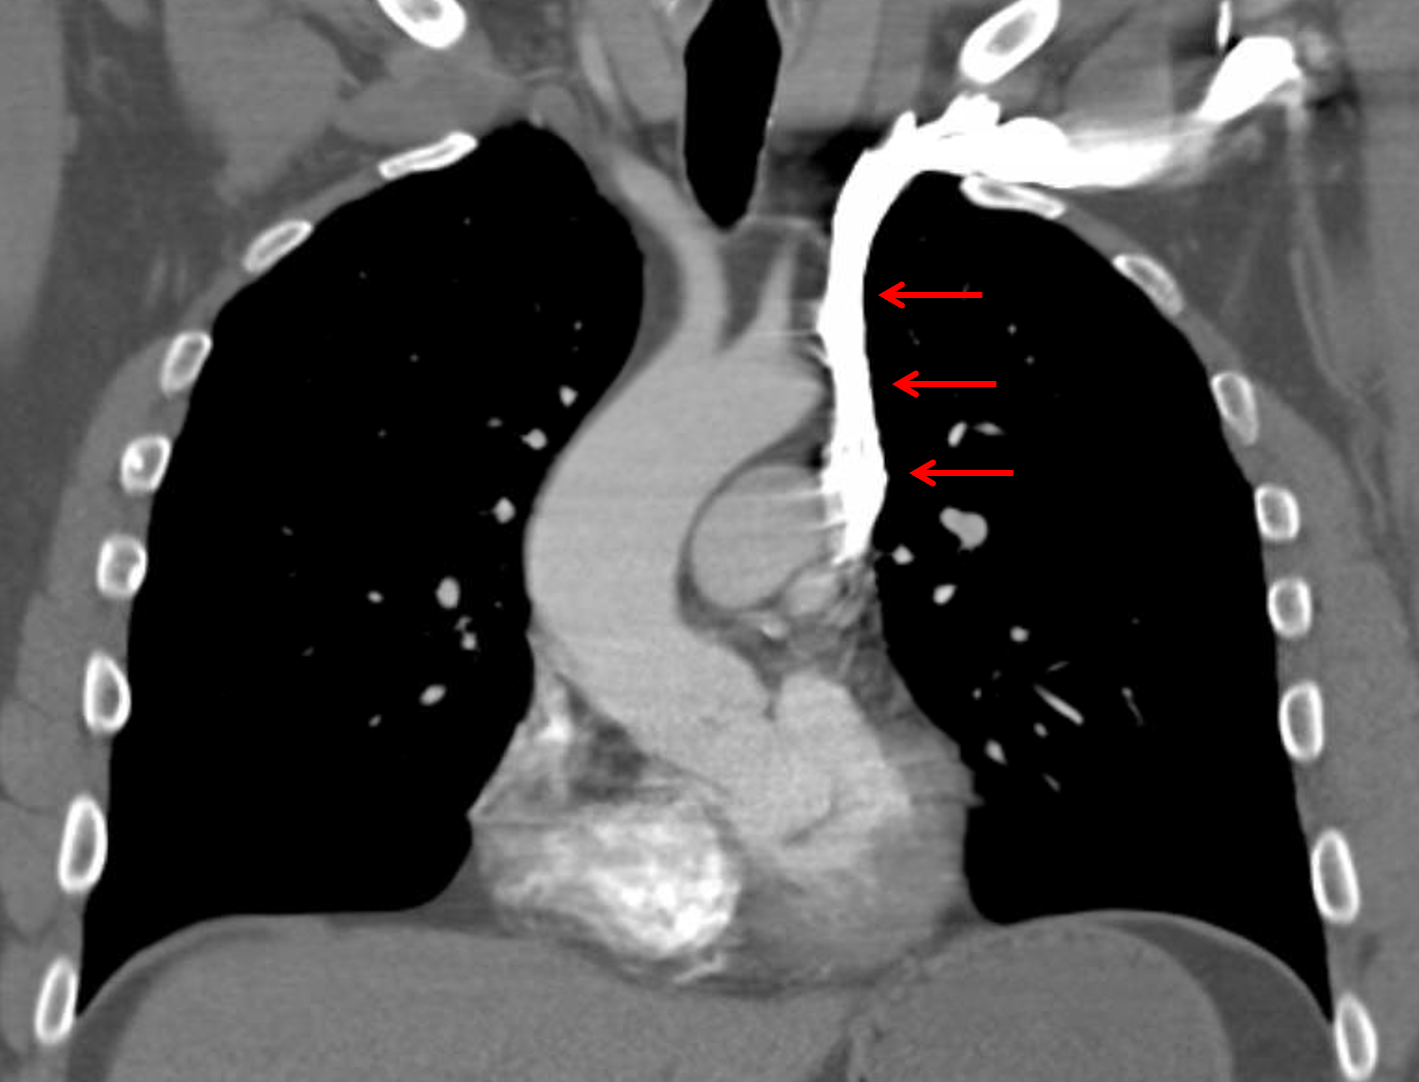

Age: 50

Sex: Male

Indication: Hemoptysis, current smoker

Sample ReportFindings suggest bronchitis and respiratory bronciolitis given the patient’s smoking history, which is the likely etiology for hemoptysis. No pulmonary mass.

Left SVC draining into the coronary sinus and absent right SVC, anatomic variant. This variant anatomy should be taken into consideration with any future central venous access.